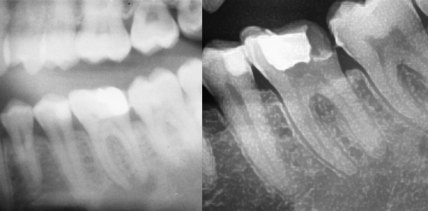

Parodontologie 21.02.2011

Diabetes mellitus – eine systemische Erkrankung

Diabetes mellitus ist eine vielfältige genetisch bedingte endokrine Erkrankung, welche durch Glukoseintoleranz charakterisiert ist. Hauptmerkmal dieser Erkrankung ist ein erhöhter Blutglukosespiegel, der ein Resultat verringerter Insulinproduktion, Insulindysfunktion oder fehlender Rezeptorsensibilität an den Zelloberflächen ist. Welche Rolle Parodontitis dabei spielt, klärt Dr. Antina Schulze im nachfolgenden Beitrag. Diabetes mellitus hat vielerlei negative Auswirkungen auf weiterlesen